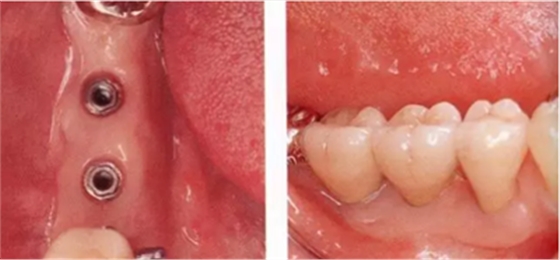

Type2-Class2

的病例(病例6):由于牙槽嵴的角化齦寬度不足,因此頰側(cè)進行FGG、舌側(cè)進行APF的病例。

▲圖8-1,2

圖8-1 缺損牙槽嵴的頰側(cè)幾乎沒有角化齦。

圖8-2 (牙合)面照。從牙槽嵴到舌側(cè)的區(qū)域內(nèi)有一定程度的角化齦,但是角化齦寬度不足。(Type2-Class2)。

▲圖8-3,4

圖8-3 在腭側(cè)采集移植片,然后在頰側(cè)進行FGG。

圖8-4 將原有的舌側(cè)角化齦移向根尖側(cè),以增大角化齦。

▲圖8-5,6

圖8-5 佩戴上部基臺時的(牙合)面照。獲得了充足的角化齦。

圖8-6 佩戴最終修復(fù)體時的(牙合)面照。